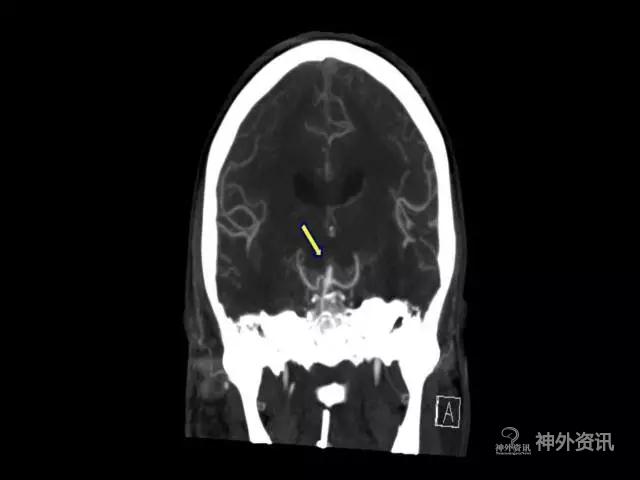

但对于一些特殊类型的BA或SCA,如瘤颈高于后床突1cm以上,就可以采用LSO这种常规简便侵袭性较小的入路(图1、2)。

图1. 破裂的基底动脉尖动脉瘤(瘤颈>后床突1cm)。(注:本文图片均引自芬兰Juha Hernesniemi教授)

图2. 破裂的基底动脉尖动脉瘤(瘤颈>后床突1cm)。